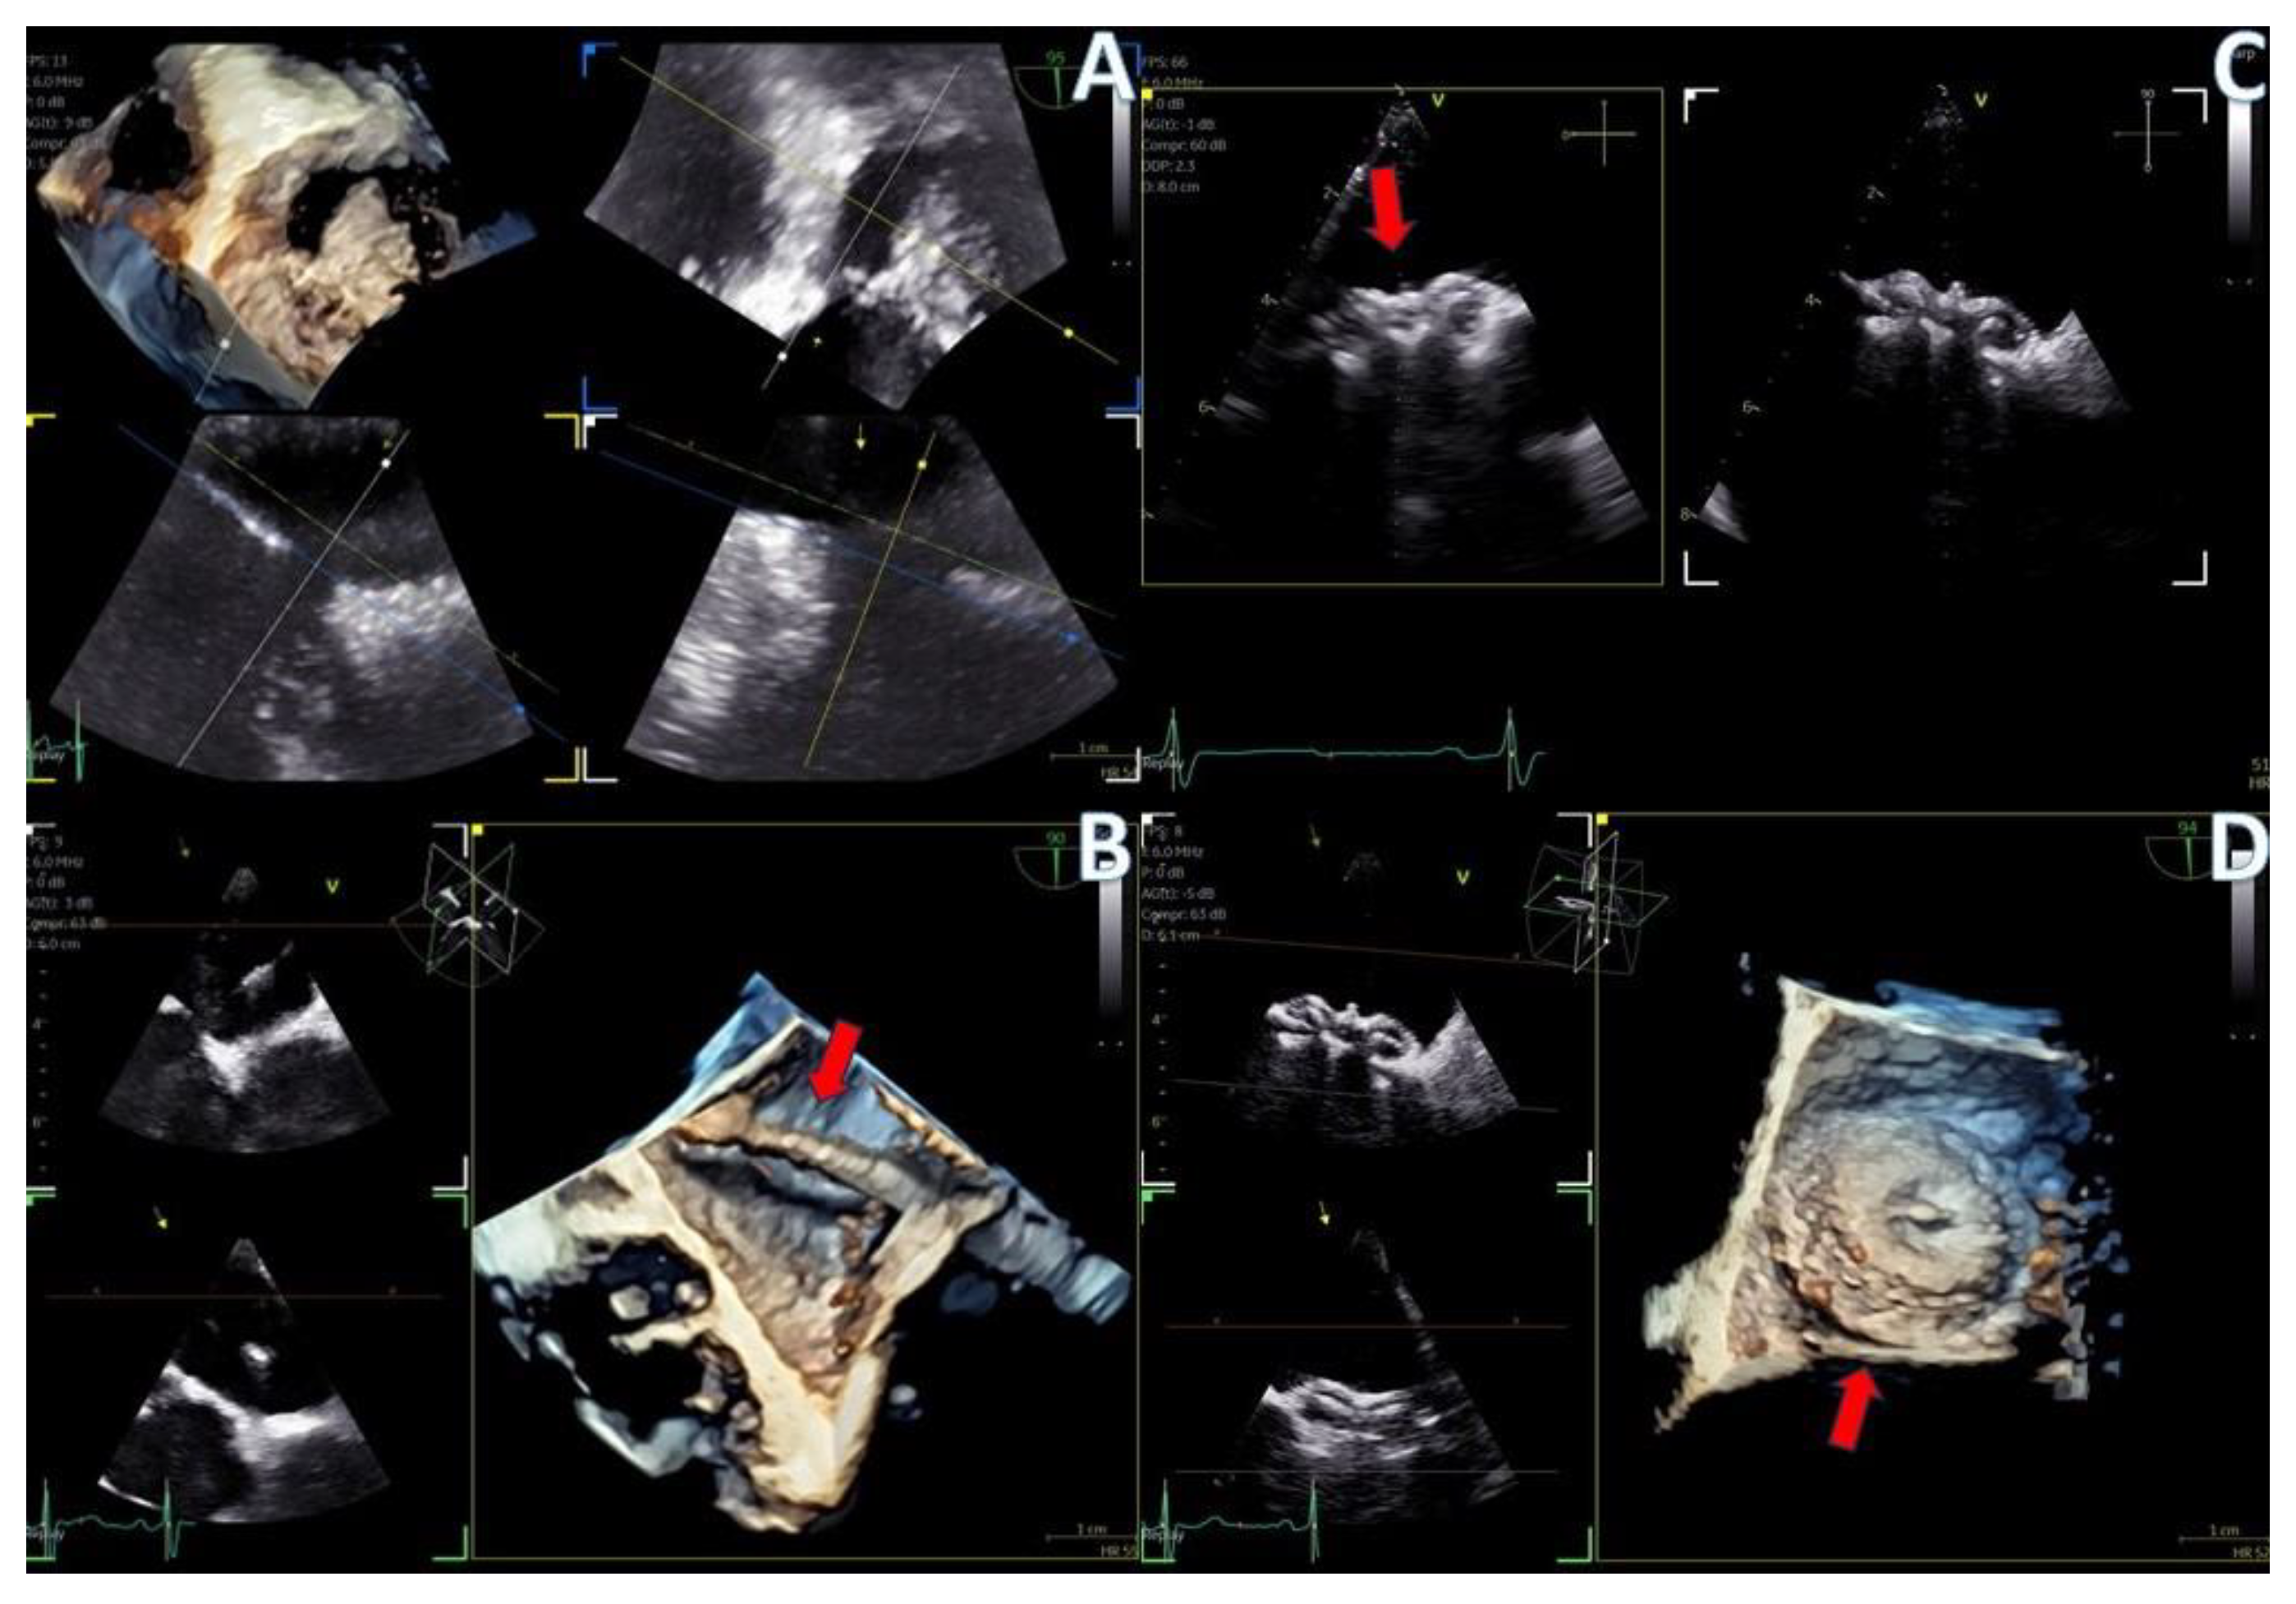

Figure 4.

(A) A 4D demonstration of a true−bicuspid aortic valve (red arrow), (B) Biplane 2D demonstration of a true−bicuspid aortic valve (red arrow), (C) Chronic dissection of descending aorta (red arrow showing the wall of the true lumen), (D) 3D volume-rendered color Doppler image showing the true (right arrow) and the false lumen (left arrow).

Regarding imaging quality, almost all patients exhibited excellent images without any compromise in resolution, obviating the need to confirm findings using the standard TEE probe (Figure 3 and Figure 4, video S5). Despite the one patient requiring additional sedation due to intense pharyngeal reflex, the quality of images obtained remained consistent across all cases. In 22 cases out of 30 included in this study, the 2D and 3D imaging quality received a score of 5 suggesting excellent imaging totally equal to the one acquired with the adult probe. In four cases, 2D and 3D images were commented as good with a score of 4 and in another four cases, while the 2D images were excellent, 3D images were again mentioned to be good, almost equal to the standard probe but not exceptional enough to receive a grade of 5 (Table 3).